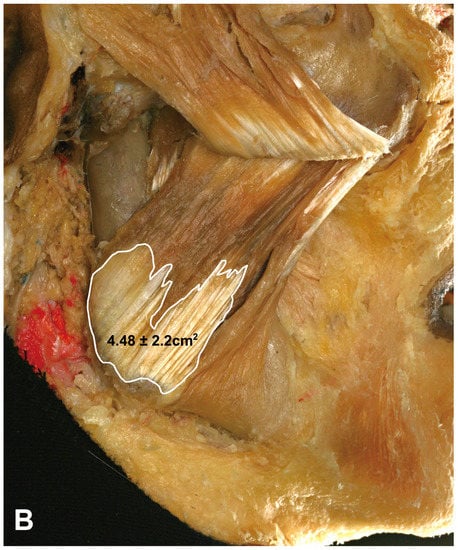

The proportion of the DIT in the superficial part of the masseter was measured using an image analysis program. The area of the superficial part of the masseter was 22.22 ± 4.2 cm2 (mean ± SD), and that of the DIT was 4.48 ± 2.2 cm2, thereby constituting approximately 22% of the superficial part of the masseter (19% in the Korean cadavers and 25% in the Thai cadavers) (Figure 4).

Figure 4. Proportions of the DIT in the superficial part of the masseter. The surface area of the superficial part of the masseter muscle was 22.22 ± 4.2 cm2 (A), and the DIT area within the masseter muscle was 4.48 ± 2.2 cm2 (B), hence constituting 22% of the superficial part of the masseter.